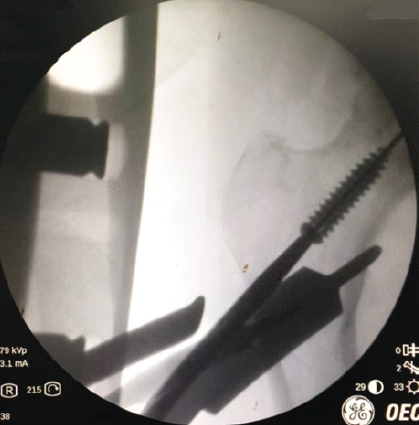

Direct attempts to grasp the screw risked enlarging the core tract. As shown in Fig. 2, gentle retrieval using the screwdriver over the guide wire was initially attempted.

Figure 2: Attempting removal with gentle counterclockwise screwing with a screwdriver.

This did not work as force is required to mate the screwdriver tip to the screw head, which would lead to further burial of the screw. Subsequently, a guide wire was bent to create a hook at the end and insertion across the interference was attempted (Fig. 3).